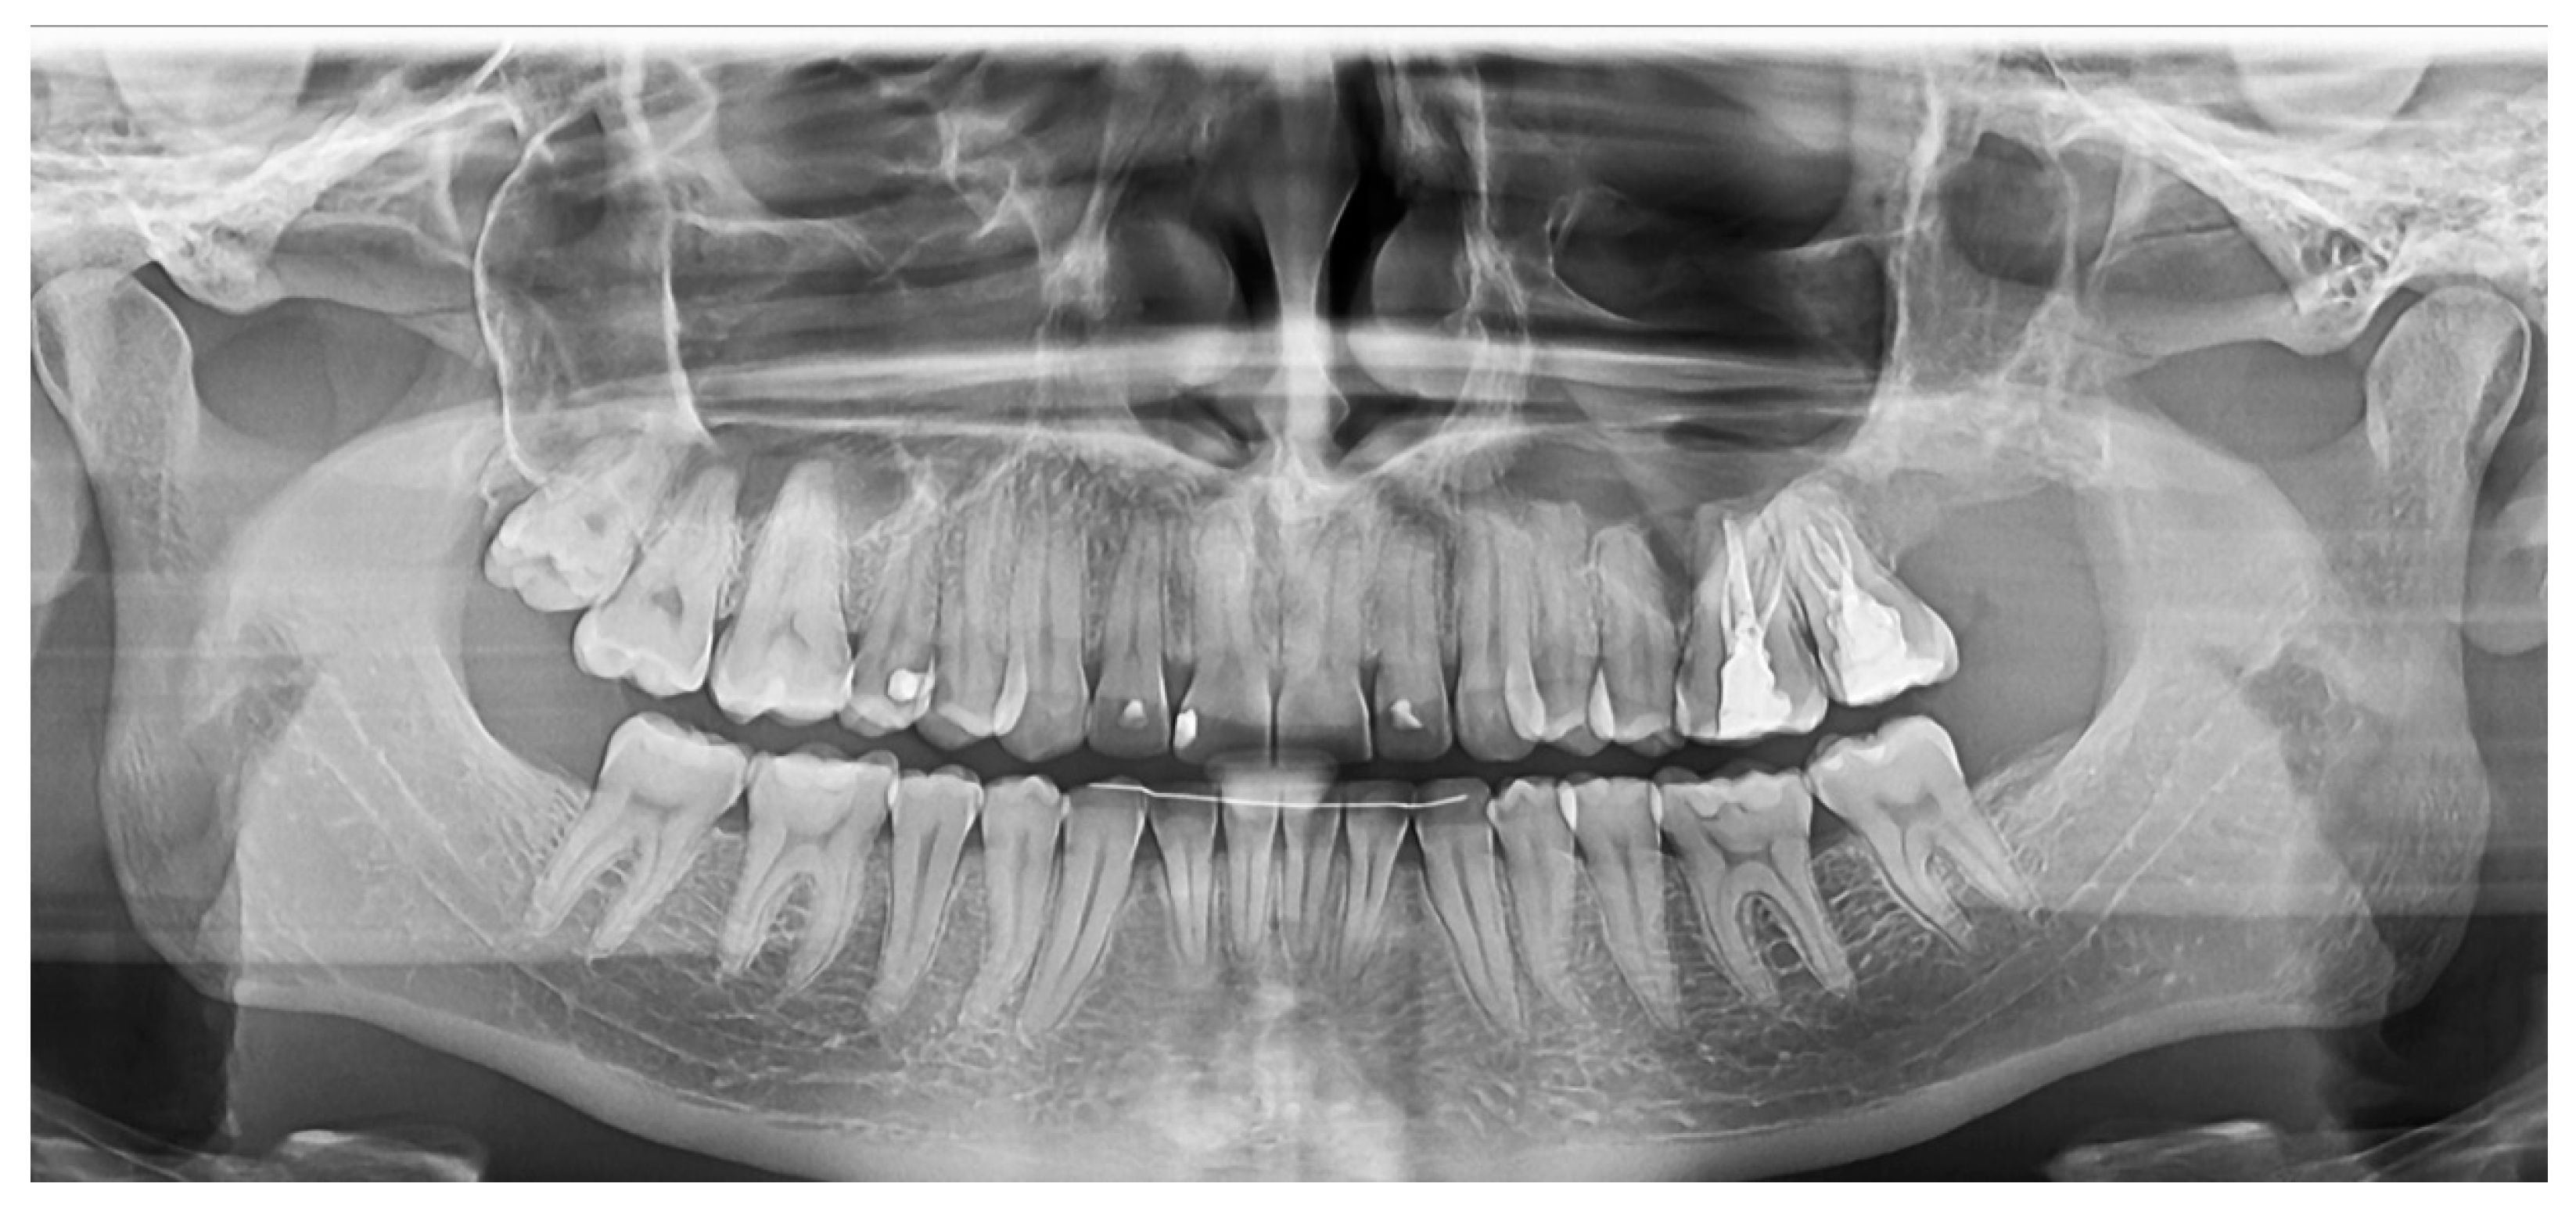

2.2.1. Case 1

2.2.2. Case 2

2.2.3. Case 3